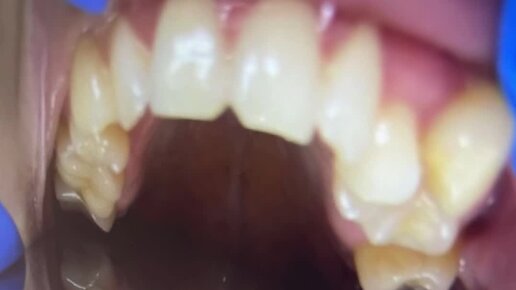

Возможности современной ортодонтии

Ортодонтия

Далее: Установка брекет-системы на обе челюсти у юной пациентки